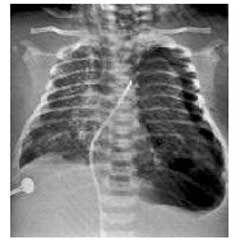

- X-quang:

- Nhu mô phổi thông khí không đều, có hạt đậm bờ không rõ, tập trung nhiều ở rốn phổi. Các vùng xẹp phổi và khí thủng rải rác không đều ở hai phổi.

- Có thể có tràn khí lồng ngực, ứ khí ở phổi với biểu hiện vòm hoành bị đẩy dẹt xuống.

Hình ảnh phân su trong cây khí - phế quản - phế nang |